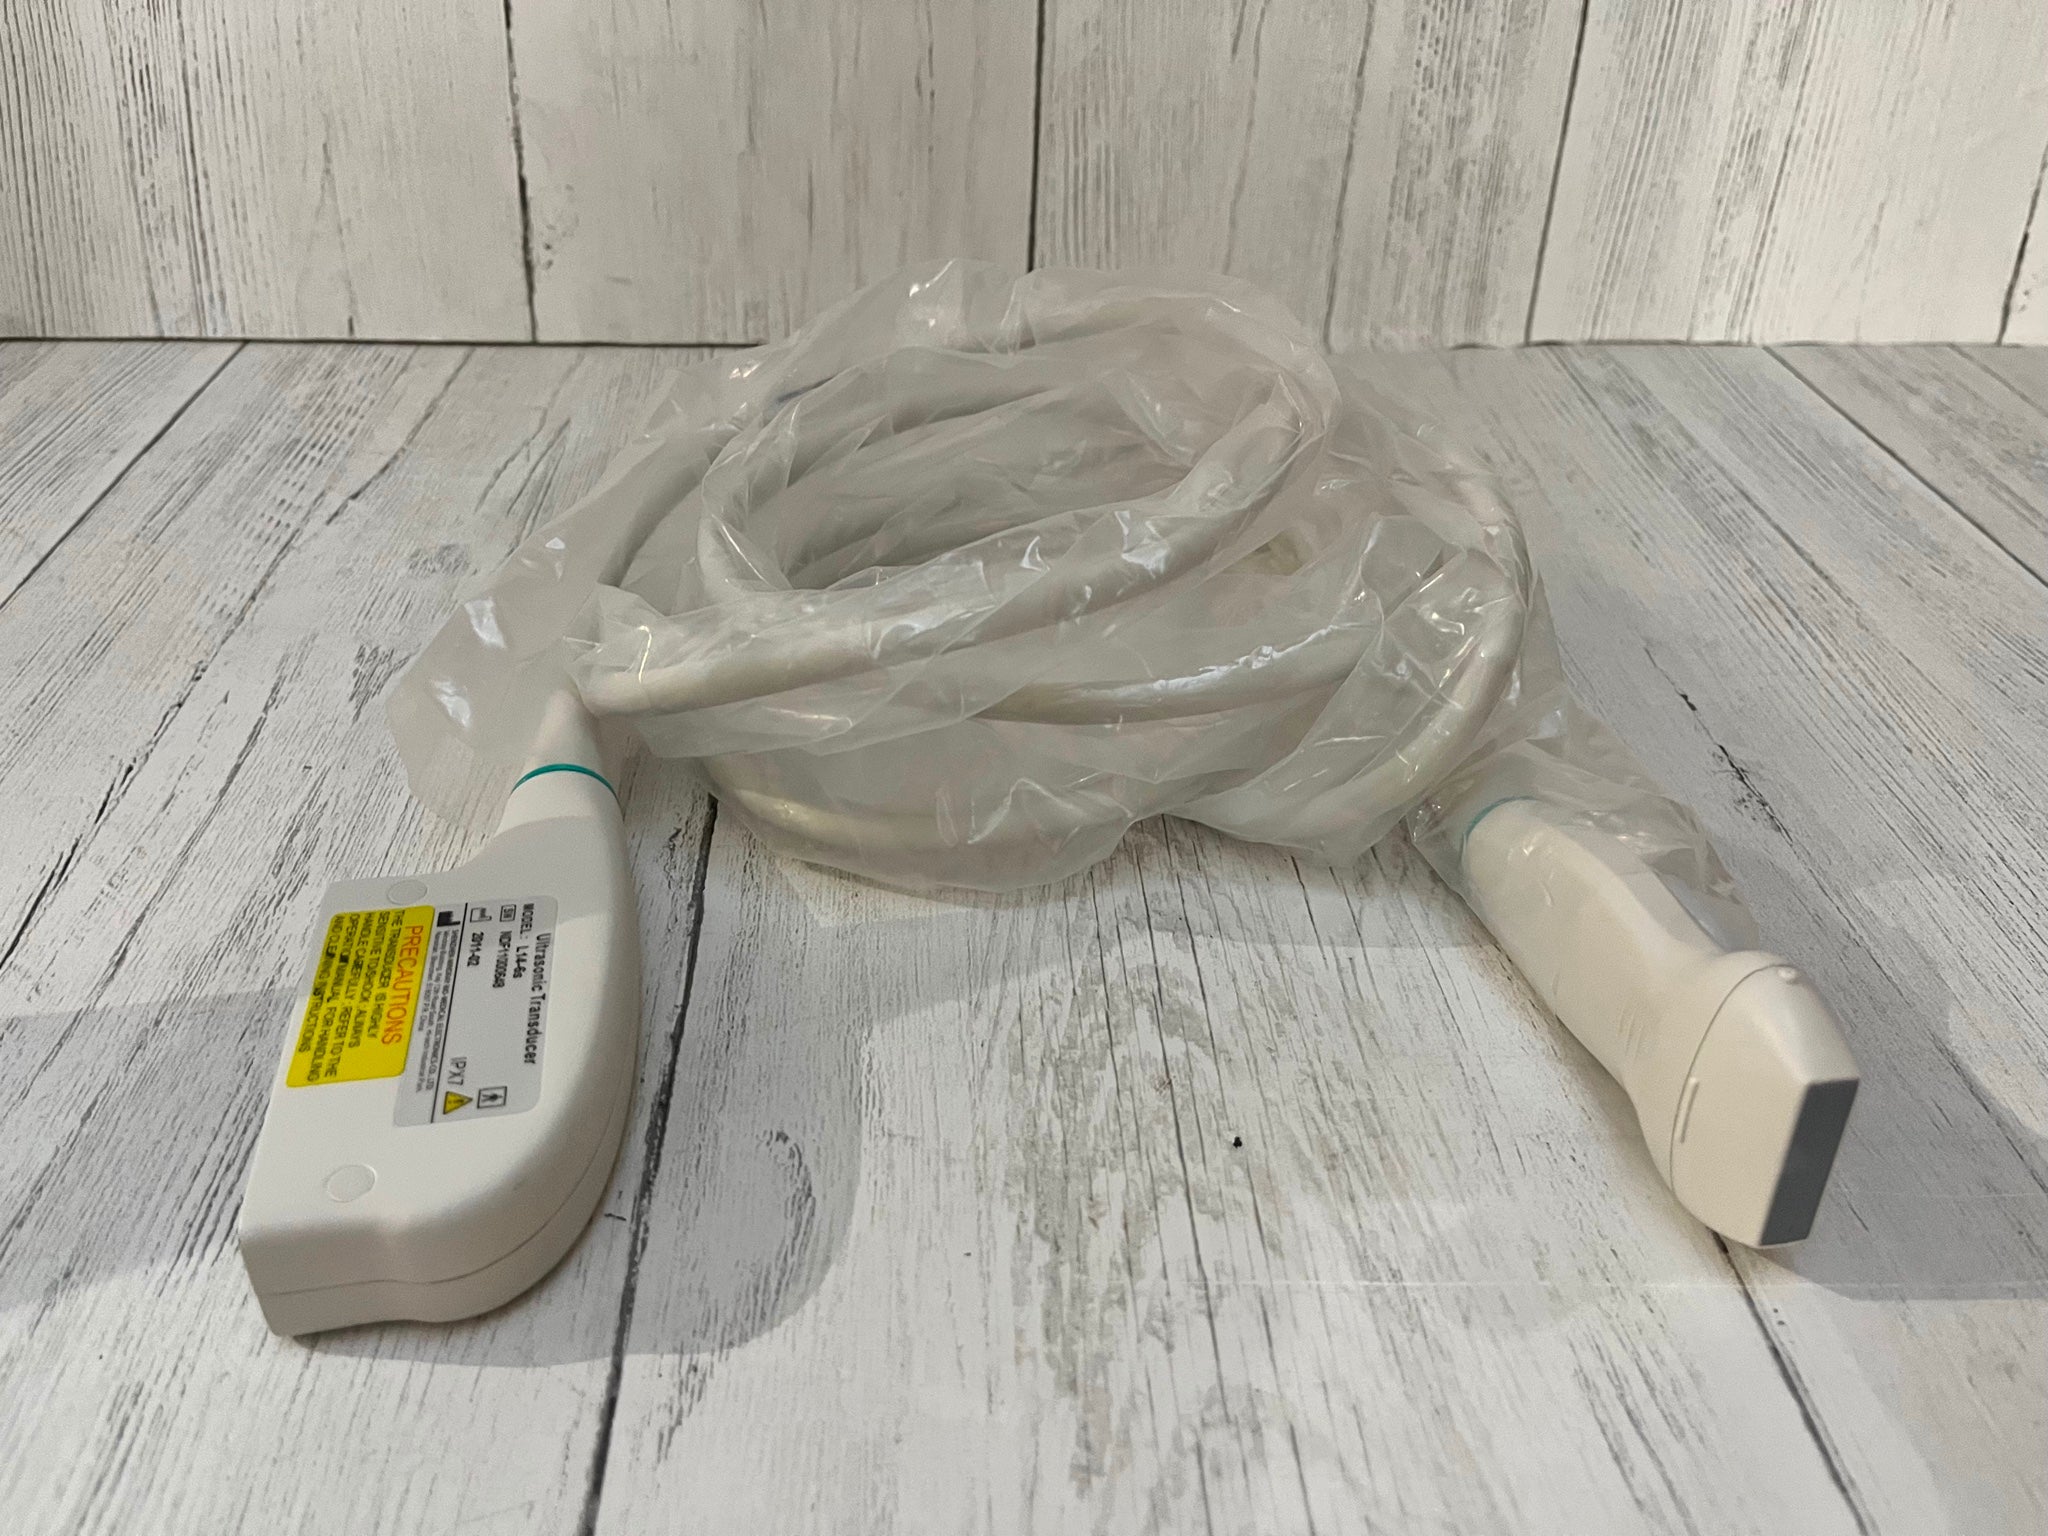

The system typically comes with a probe that is specifically designed to provide clear imaging of the animal’s reproductive organs, allowing the veterinarian to determine the pregnancy status, number of fetuses, and their development stages. With real-time imaging and high-resolution capabilities, it helps in assessing the health of the fetus and identifying potential complications. The machine is lightweight and portable, making it easy to use on farms or in field environments. This ultrasound system is a valuable tool for ensuring the health and wellbeing of pregnant animals and managing breeding programs efficiently.